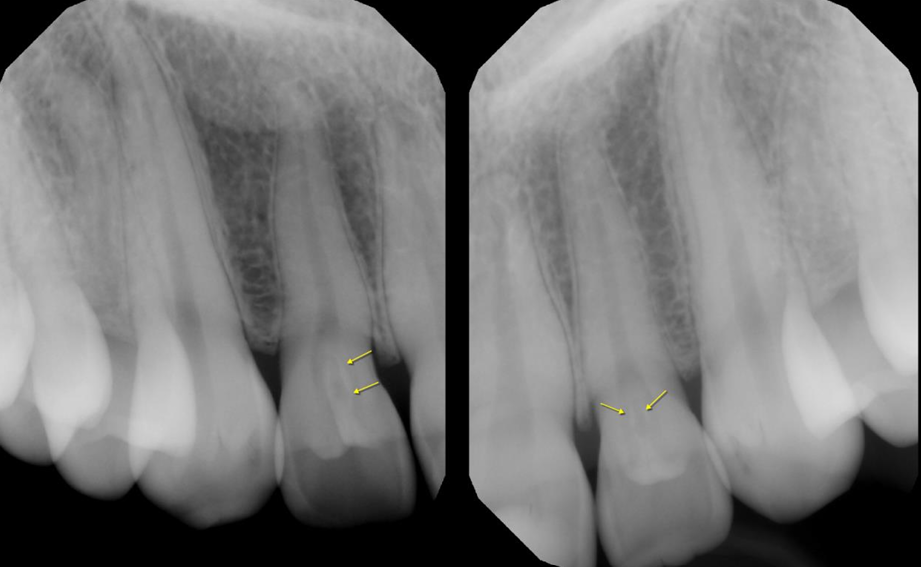

A 16-year-old female came in for a routine examination, upon clinical examination, periapicals of the maxillary anterior region were ordered.

Radiographic findings: Radiographs reveal well-defined radiolucent infoldings within the crown of the lateral incisors, outlined by a thin radiopaque enamel/dentin border. The invaginations extend almost up to the root.

Interpretation: Dens invaginatus in the maxillary lateral incisors

Treatment: In the absence of periapical inflammatory signs, prophylactic sealing is recommended.